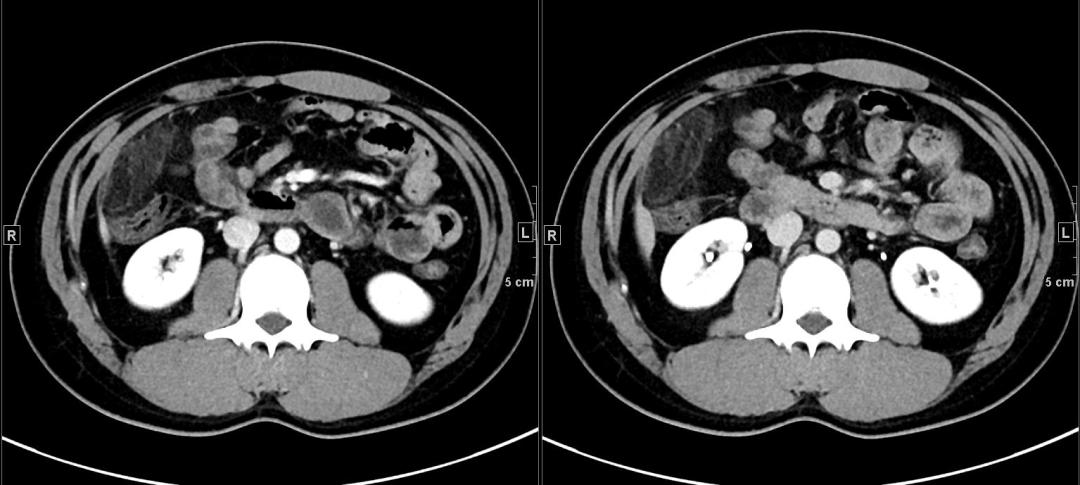

最后,做了腹盆增强CT。典型的图像如下:

上面4图分别为:平扫、动脉期、门脉期、延迟期

影像表现:于升结肠前方可见一不规则团块状脂肪密度影,周围脂肪密度增高,升结肠周围可见饱满淋巴结,邻近肠壁有轻微增厚,无明显脓肿及肠梗阻征象。

诊断:升结肠肠脂垂炎。